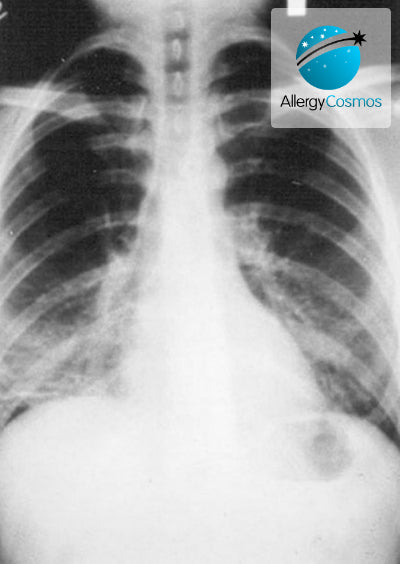

What is Pneumonia?

Pneumonia is a fairly common lung condition which is potentially very serious. It was once greatly feared because of its high mortality rate but in modern times it is generally...